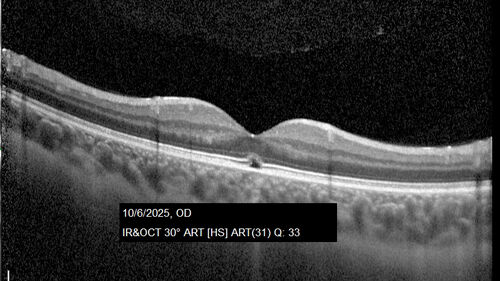

Acute Retinal Pigment Epitheliitis (Krills disease)

15 year old with sudden central vision loss in one eye. The vision loss persisted though for at least 6 months (which may be a laser injury)